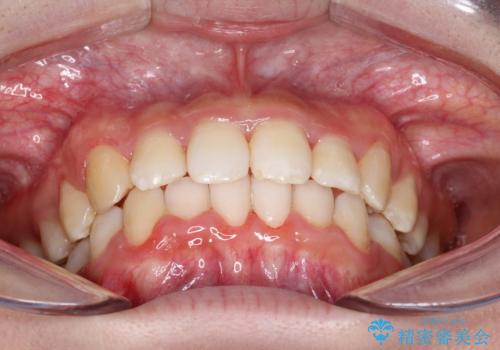

重度のガタガタのインビザラインによる非抜歯矯正

- 全体的なガタガタを気にされて来院されました。

抜歯矯正も考えられる状態でしたが、ご本人的になるべく歯を抜かない矯正を希望されました。

奥歯を後方に移動させるのと、歯と歯の間にわずかに隙間を作ることでスペースを確保して、抜歯をせず歯を並べる計画としました。

ガタガタの度合いが大きかったので少し時間がかかりましたが、非常に協力的な患者様でしたので、抜歯をせず計画通りに治療を終えることができました。